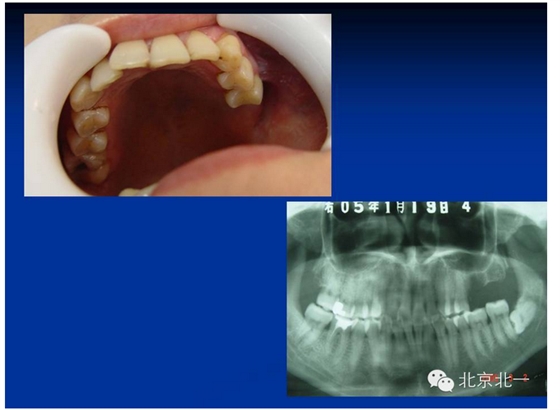

擅長:種植外科,尤其專長復雜牙種植,自體骨移植同期種植,上頜竇底內(nèi)外提升同期種植技術,美學區(qū)種植技術,即刻種植外科與即刻負重技術,軟組織成形外科種植技術及全口無牙頜ALL-ON-FOUR技術,種植并發(fā)癥和種植急癥處置等手術治療,從事口腔頜面外科,正頜外科、頜面部整形、微創(chuàng)拔牙,笑氣無痛舒適種植十余年。

往屆精彩剪影